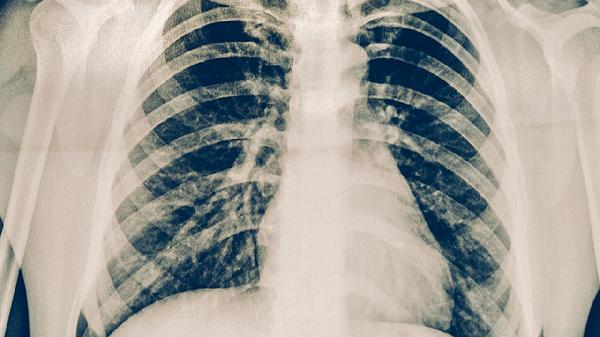

糖尿病血糖控制不佳者、矽肺患者、慢性腎功能衰竭人群更易繼發(fā)肺結(jié)核。高血糖環(huán)境利于細(xì)菌繁殖,塵肺導(dǎo)致的肺組織纖維化形成病灶溫床。需優(yōu)先控制基礎(chǔ)疾病,聯(lián)合使用鹽酸二甲雙胍緩釋片、吡嗪酰胺片等藥物進(jìn)行綜合治療。